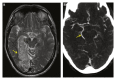

Report: A 71 year old male patient was admitted to the stroke team with seizures, headache, and confusion. Examination revealed a left sided homonymous hemianopia. Diffusion weighted magnetic resonance imaging (MRI) of the brain 36 hours into his admission revealed an acute right posterior circulation infarct with extensive haemorrhagic transformation. Duplex ultrasound three days later revealed a heavily calcified right internal carotid artery mixed echogenicity plaque with 80%-90% stenosis. Subsequent computed tomography angiography showed a large right foetal variant posterior communicating artery. Following improvement in functional status, the patient underwent uneventful carotid endarterectomy to reduce risk of future stroke.